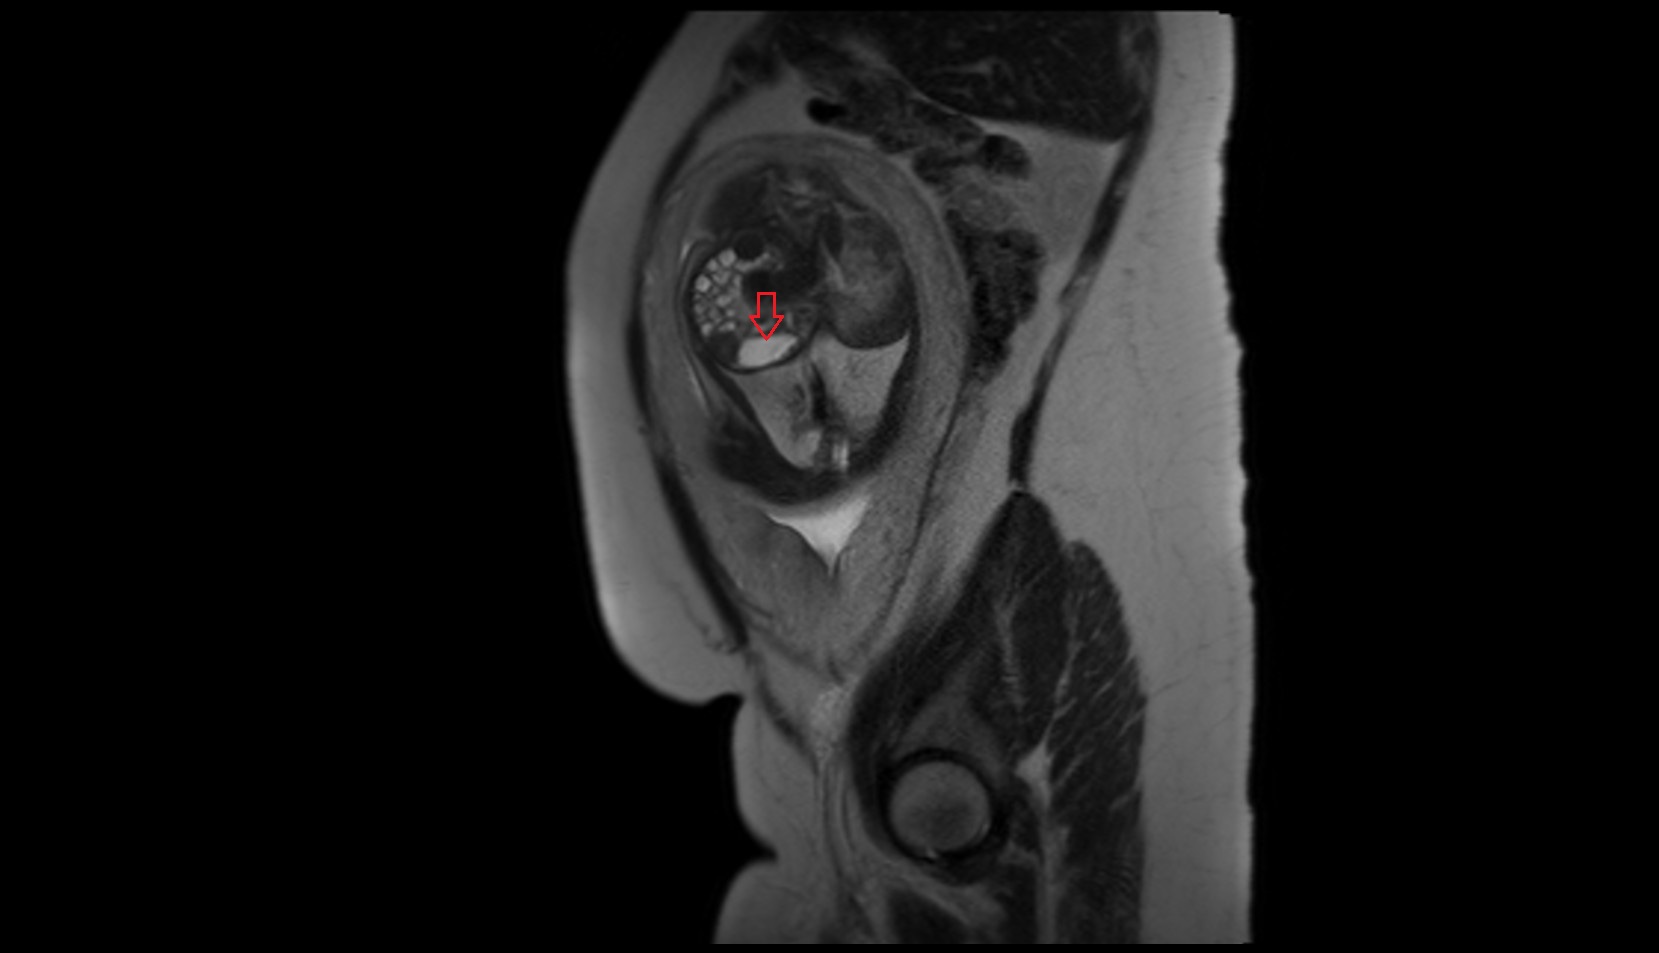

- Placenta

- Uterus (pregnancy)

- Amniotic fluid

- Umbilical cord

- Cervix in Pregnancy

- Vagina in Pregnancy

- Urinary bladder

- Uterus

- Fetal brain

- Fetal pons

- Fetal cerebellum